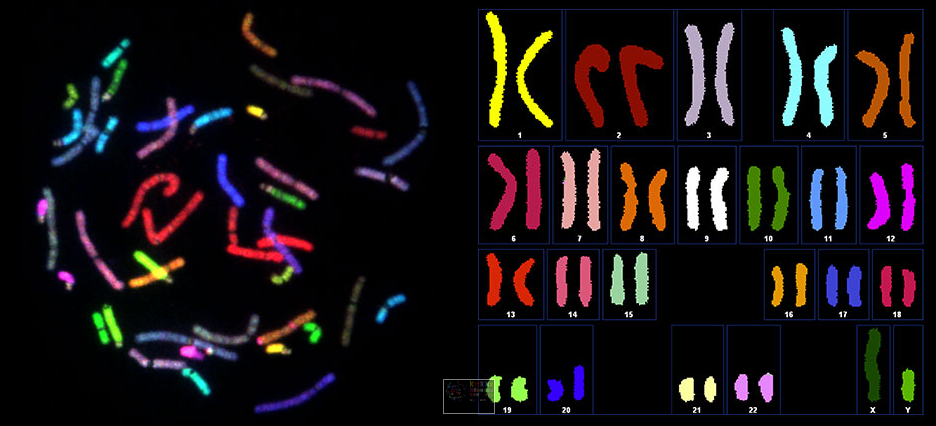

Spectral karyotype analysis / Image courtesy of Human Longevity, Inc.

Today, we’re using a broad range of AWS services for all kinds of compute and storage tasks. For example, the HLI Knowledgebase leverages a distributed system infrastructure comprised of Amazon S3 storage and a large number of Amazon EC2 nodes. This helps us achieve resource isolation, scalability, speed of provisioning, and near real-time response time for our petabyte-scale database queries and dynamic cohort builder. The flexibility of AWS services makes it possible for our customized Amazon Machine Images and pre-built, BTRFS-partitioned Amazon EBS volumes to achieve turn-up time in seconds instead of minutes. We use Amazon EMR for executing Spark queries against our data lake at the scale we need. AWS Lambda is a fantastic tool for hooking into Amazon S3 events and communicating with apps, allowing us to simply drop in code with the business logic already taken care of. We use Auto Scaling based on demand, and AWS OpsWorks for managing a Docker pipeline.

When Human Longevity, Inc. launched in 2013, our founders recognized the challenges ahead. A genome contains all the information needed to build and maintain an organism; in humans, a copy of the entire genome, which contains more than three billion DNA base pairs, is contained in all cells that have a nucleus. Our goal is to sequence one million genomes and deliver that information—along with integrated health records and disease-risk models—to researchers and physicians. They, in turn, can interpret the data to provide targeted, personalized health plans and identify the optimal treatment for cancer and other serious health risks far earlier than has been possible in the past. The intent is to transform medicine by fostering preventive healthcare and risk prevention in place of the traditional “sick care” model, when people wind up seeing their doctors only after symptoms manifest.

Our work in developing and applying large-scale computing and machine learning to genomics research entails the collection, analysis, and storage of immense amounts of data from DNA-sequencing technology provided by companies like Illumina. Raw data from a single genome consumes about 100 gigabytes; that number increases as we align the genomic information with annotation and phenotype sources and analyze it for health insights.